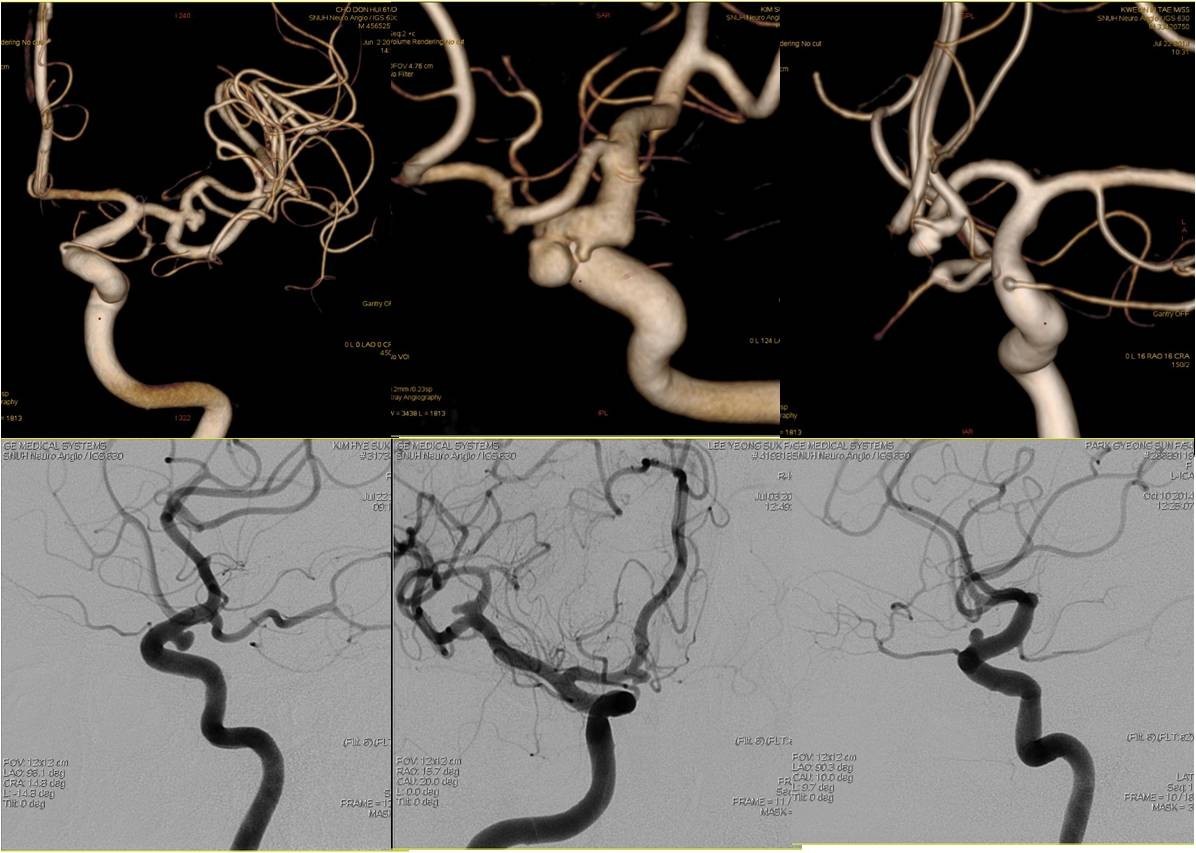

(二)颅内动脉瘤栓塞术

病例1:前交通动脉动脉瘤(Acom-An)

》男性,40岁,因头痛6个月、加重1天入院,头痛为全脑胀痛,疼痛较剧烈,为求进一步诊治就诊于我院门诊,按“头痛待查”收入我院。

》入院时查体:神经系统查体未见阳性定位体征。

》入院后行头颅MRA发现前交通动脉囊状动脉瘤。

病例2:后交通动脉动脉瘤(Pcom-An)

》女性,59岁,因一过性意识不清伴头痛20天入院,头痛为全头炸裂样疼痛,于当地医院检查后诊断为“蛛网膜下腔出血”保守治疗20天,现仍有头痛,为求进一步诊治入院。既往有高血压病病史40年,血压控制不详。

》入院时查体:项强3横指。

术前、术后DSA对比

》DSA检查发现右侧后交通动脉动脉瘤,全麻下行颅内动脉瘤栓塞术。